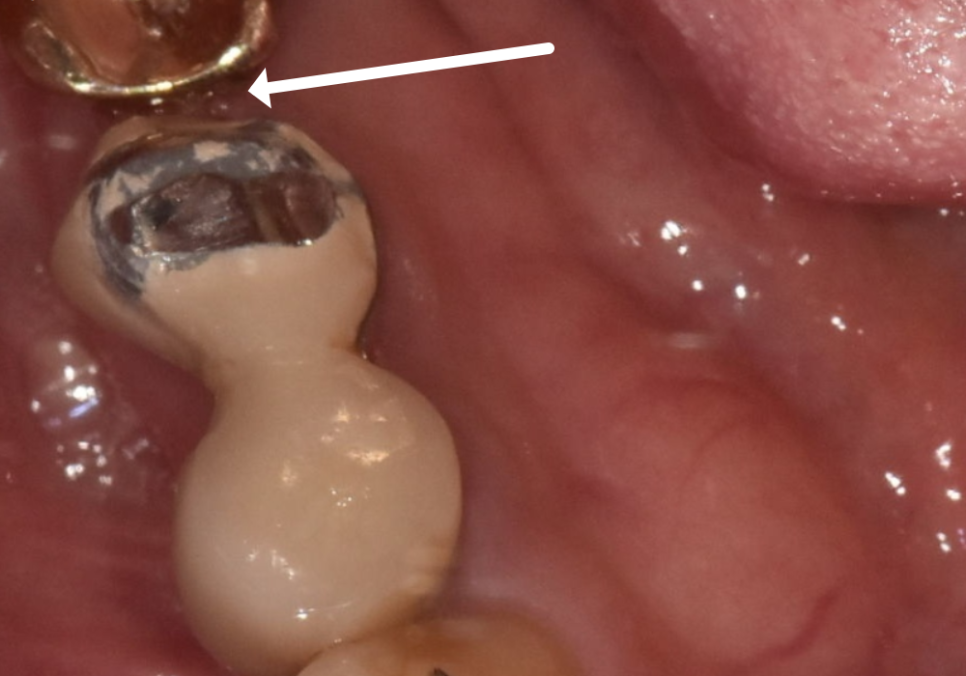

임플란트 옆에 도자기로 씌워둔 치아(#45)의

보철물이 깨져 있었는데,

251118

그 틈으로 음식물이 계속 끼어 들어가면서

치아 뿌리 깊숙이 충치가 생긴 상태였어요.

문제는 옆 치아(#45)였는데요.

보철물을 뜯어보니 충치가 깊어

남아있는 치아량이 적어

안타깝게도 함께 발치를 진행해야 했습니다.